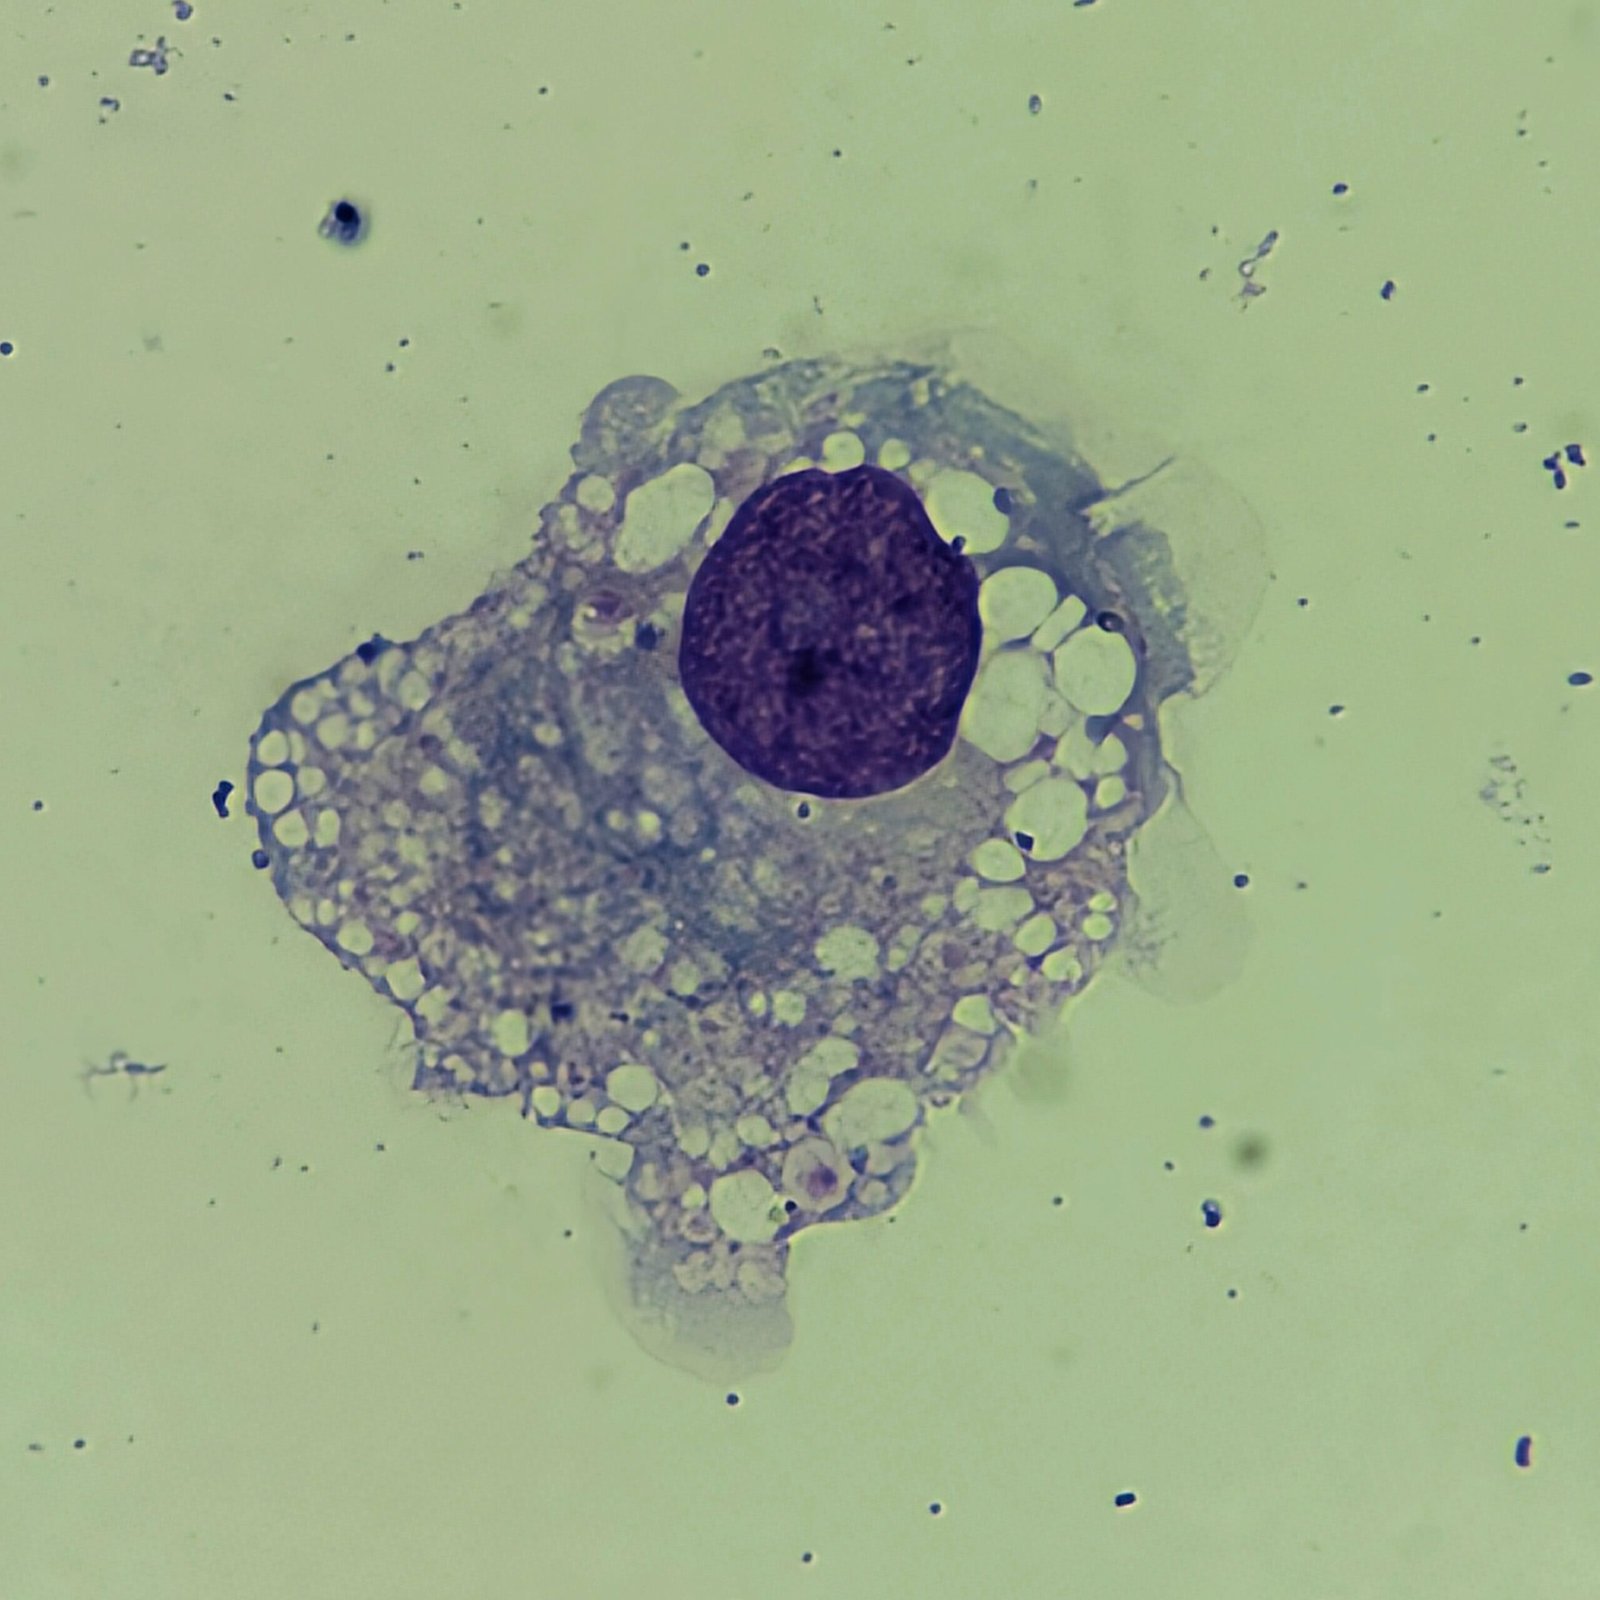

Macrophages are about the same size as mesothelial cells, so the two can often be confused. Macrophages can usually be differentiated by the presence of vacuoles and a lacey chromatin. If both cell types are present and differentiation is difficult, take a look around the slide to get an idea of each kind of morphology before starting a differential.